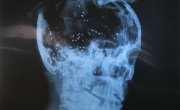

"مرآة البحرين" تكشف وثائق طبية مسربة تدين وزارة الداخلية ومستشفى السلمانية في مقتل الشهيد يعقوب

2012-01-27

مرآة البحرين (خاص): حصلت "مرآة البحرين" على نتائج التحليلات التي أجريت للشهيد الشاب محمد إبراهيم يعقوب (18 عاما) في مستشفى السلمانية بعد دهسه وضربه من قبل قوات الأمن.